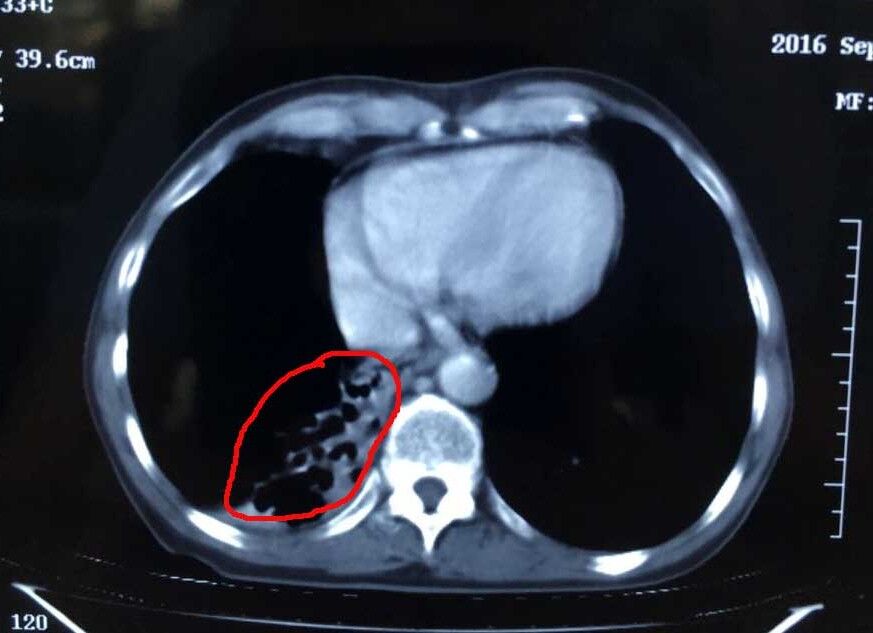

術前的楊清貴心情十分忐忑,但聽了醫(yī)生一番話后又恢復了平靜。“林菁醫(yī)生耐心地跟我們解釋了治療有哪些風險,如腫瘤靠近肺門以及氣管,冷凍治療可能會造成出血、咳血、氣胸等,但很快又給我們服下定心丸,‘醫(yī)院每天都做5-6臺這樣的手術,手術的專家經(jīng)驗都十分豐富,出現(xiàn)并發(fā)癥的情況極少。’”張英友說道。據(jù)了解,經(jīng)過近3個月的綜合治療,目前楊清貴的腫瘤幾乎全部消失,胃口、睡眠等恢復良好,身體與常人無異。

腫瘤治療后